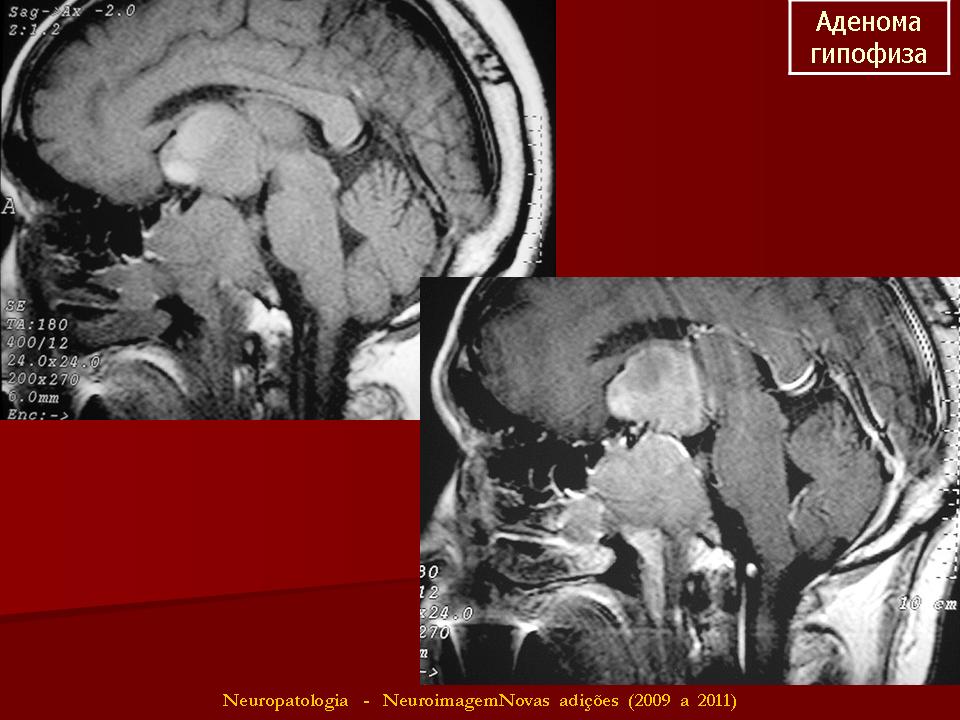

ГМ. Аденома гипофиза 1. +

Аденома гипофиза.